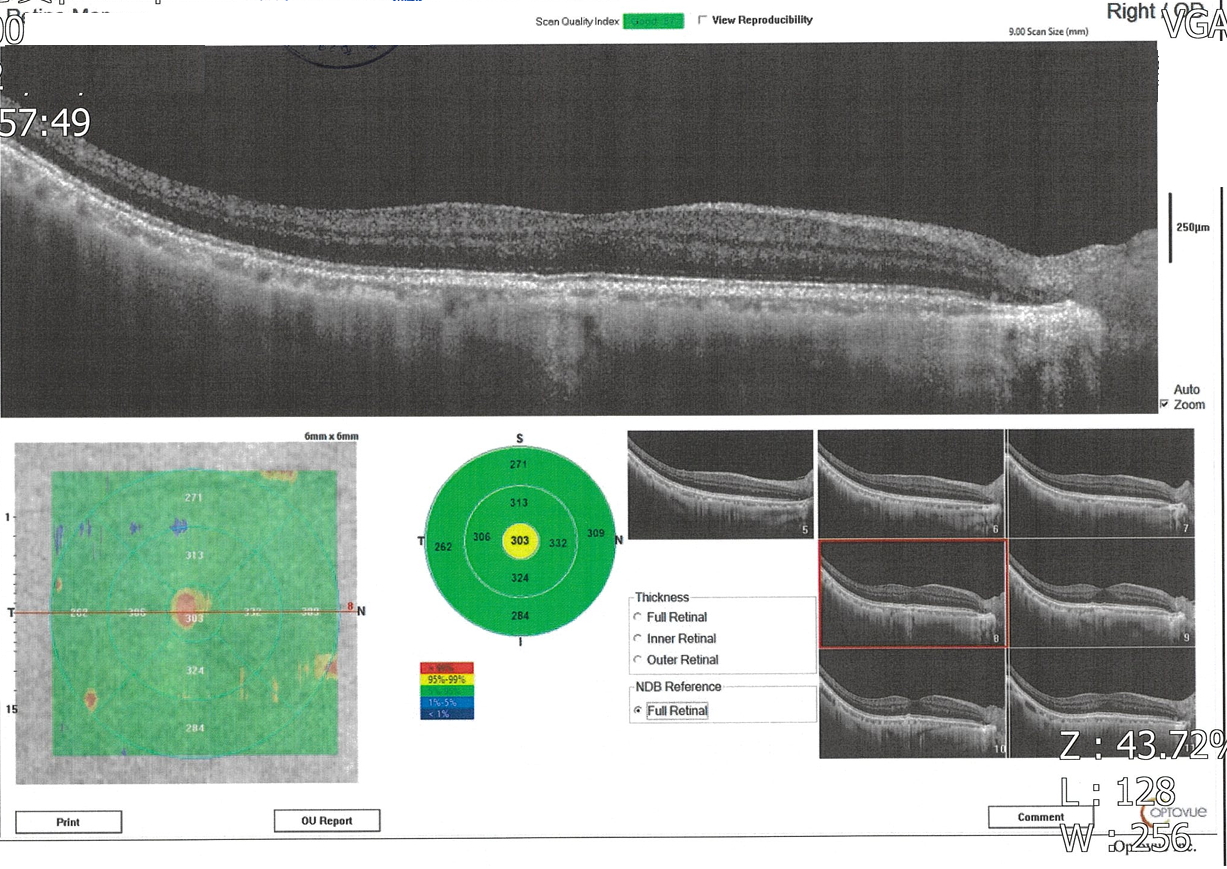

因為左眼在暗處往左看會出現垂直閃光而前往醫院就診,麻煩版主幫忙看一下報告,請問確定是青光眼?嚴重程度?

雙眼杯盤比及視網膜厚度大致正常,但左眼視野敏感度似乎整體性的下降,通常這和白內障比較有關,火勢其他問題,青光眼不會有閃光現象,所以要讓醫師檢查一下眼底,看有沒有視網膜剝離或裂孔,如果你接近50歲左右,也有可能是玻璃體老化液化而拉扯到視網膜,產生閃光